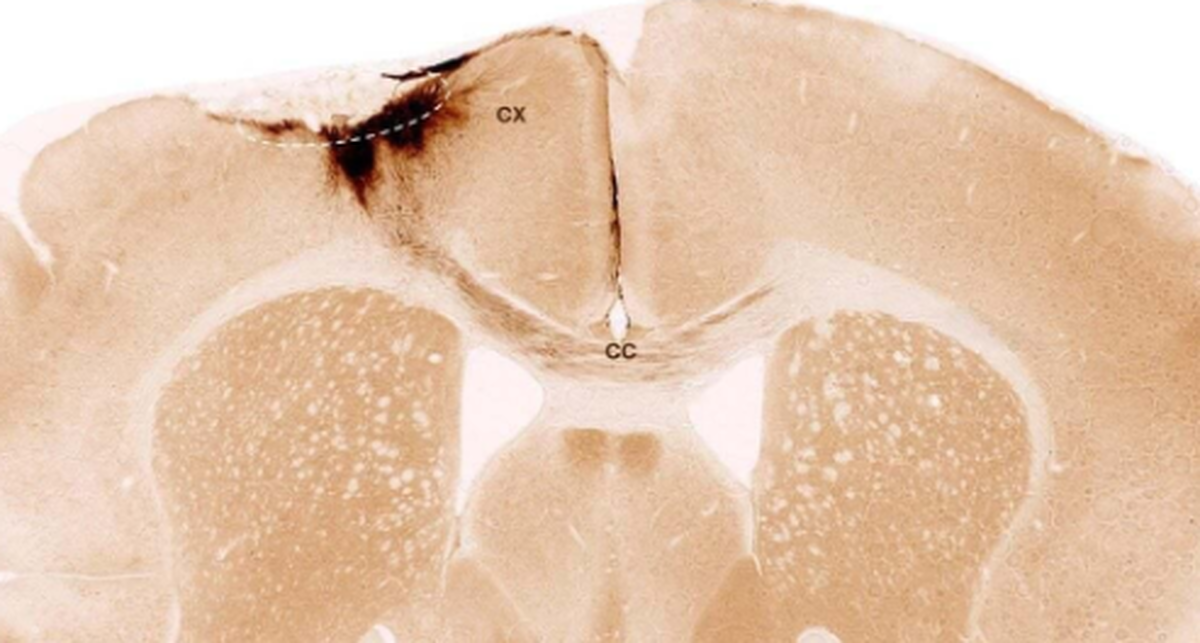

یک هفته پس از سکته سلول‌های بنیادی به ناحیه آسیب‌دیده مغز موش‌ها پیوند زده شد. بررسی‌ها با روش‌های تصویربرداری و بیوشیمیایی نشان داد که سلول‌ها تا پایان دوره ۵ هفته‌ای آزمایش زنده ماندند و بیشتر آنها به نورون تبدیل شدند؛ نورون‌هایی که با سلول‌های عصبی موجود نیز ارتباط برقرار کردند.

محققان علاوه بر نورون‌سازی، نشانه‌های دیگری از بازسازی مشاهده کردند: تشکیل رگ‌های خونی تازه، کاهش واکنش‌های التهابی و بهبود یکپارچگی سد خونی-مغزی. همچنین توان حرکتی موش‌ها که به‌دلیل سکته مختل شده بود، با پیوند سلول‌های بنیادی بهبود یافت. این موضوع با تحلیل الگو‌های حرکتی موش‌ها به کمک هوش مصنوعی تأیید شد.